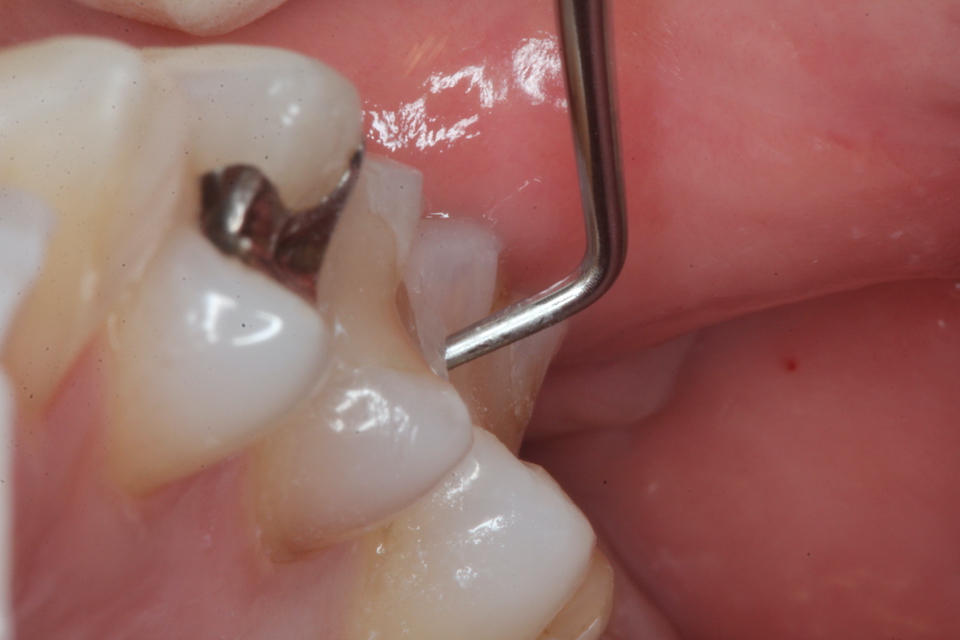

下顎7番の頬側歯茎部カリエスの原因 2025.06.04